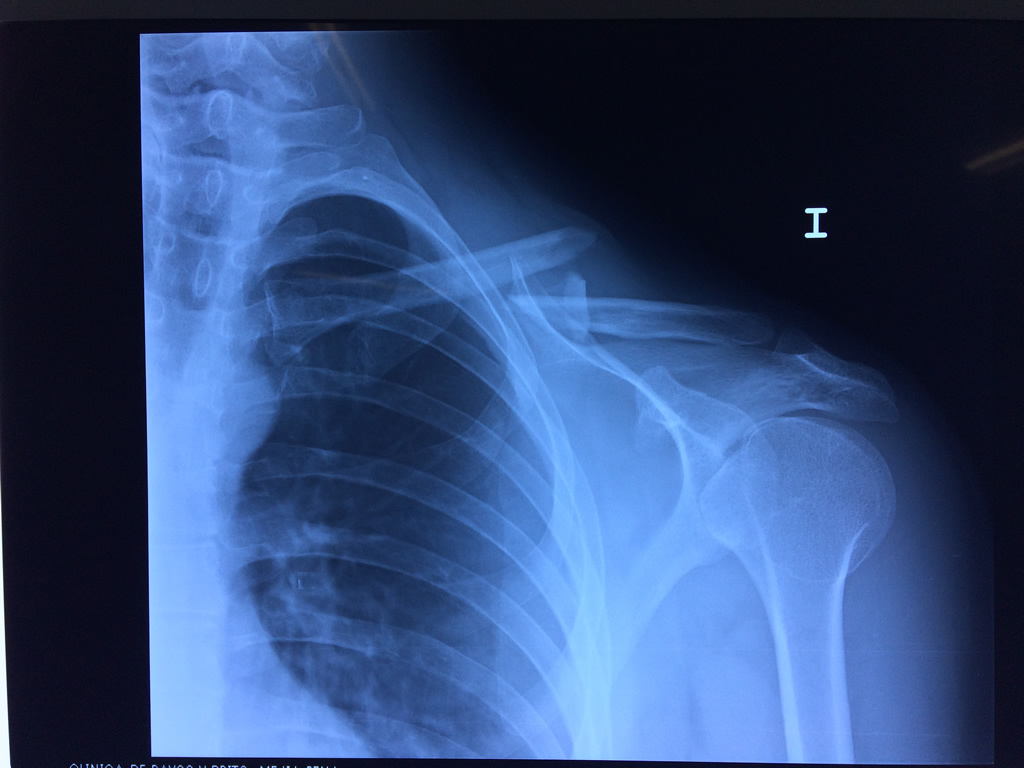

Cirugías de Húmero - Clavícula

La clavícula es un hueso largo, con forma de "S" itálica, situado en la parte anterosuperior del tórax. Junto con la escápula forman la cintura escapular. Se puede palpar por toda su longitud y se extiende del esternón al acromion de la escápula, siguiendo una dirección oblicua lateral y posterior.